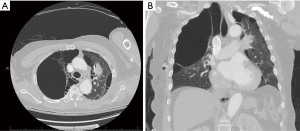

Over the next 1.5 years, the patient reduced his smoking and participated in pulmonary rehabilitation. His PFT at this time demonstrated moderately severe obstructive airway disease (Table 1). Repeat CT imaging showed minimal change in the size of his large bulla (Figure 2). The patient continued to follow up in clinic for another 8 months without a significant change in his imaging, PFT, oxygen requirement, or symptoms. He presented at this time for elective VATS bullectomy and wedge resection. His giant bulla was visualized to be located in the right upper lobe and occupied >50% of the hemithorax. This was removed and sent for pathology, which was consistent with lung parenchyma. The patient was also noted to have medium-sized bullae present in the right middle lobe. Two wedge resections were performed to remove this diseased tissue. The patient tolerated the procedure well. Two chest tubes were placed, which were removed three days post-operative (post-op). Follow-up chest X-ray two weeks later demonstrated expansion of the right lung without evidence of giant bullae or pneumothorax (Figure 3, Table 2).